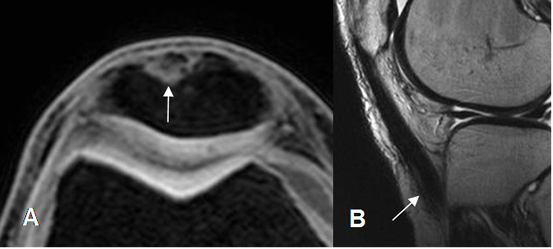

Fig 138. Cambios PostQx en tendón patelar.

A: RM axial en STIR. Defecto en la parte anterior de la patela, lugar donde se obtuvo el injerto.

B: RM sagital en T2. Cambios reparativos en la parte distal del tendón patelar.

Fig 144. Degeneración del injerto.

A: RM sagital en T1 y B: RM sagital en T2. Injerto engrosado y con alteración focal de la señal en el tercio medio, por degeneración. Ubicación normal del injerto, por detrás de la línea intercondílea.

Fig 145. Distensión del injerto.

RM sagital en T2. Injerto engrosado, poco tenso y con angulación posterior.